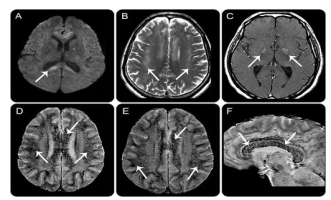

最严重的高原病,常在到达高原后48小时至5天内出现:轻微的表现为头痛、头晕及眩晕;最重的形式表现为共济失调、不同程度的意识障碍、幻觉、癫痫、视乳头水肿、视网膜出血、颅神经麻痹;有些可进展为脑疝,导致死亡。

一名高海拔脑水肿患者脑MRI显示弥漫性血管性水肿和微出血。